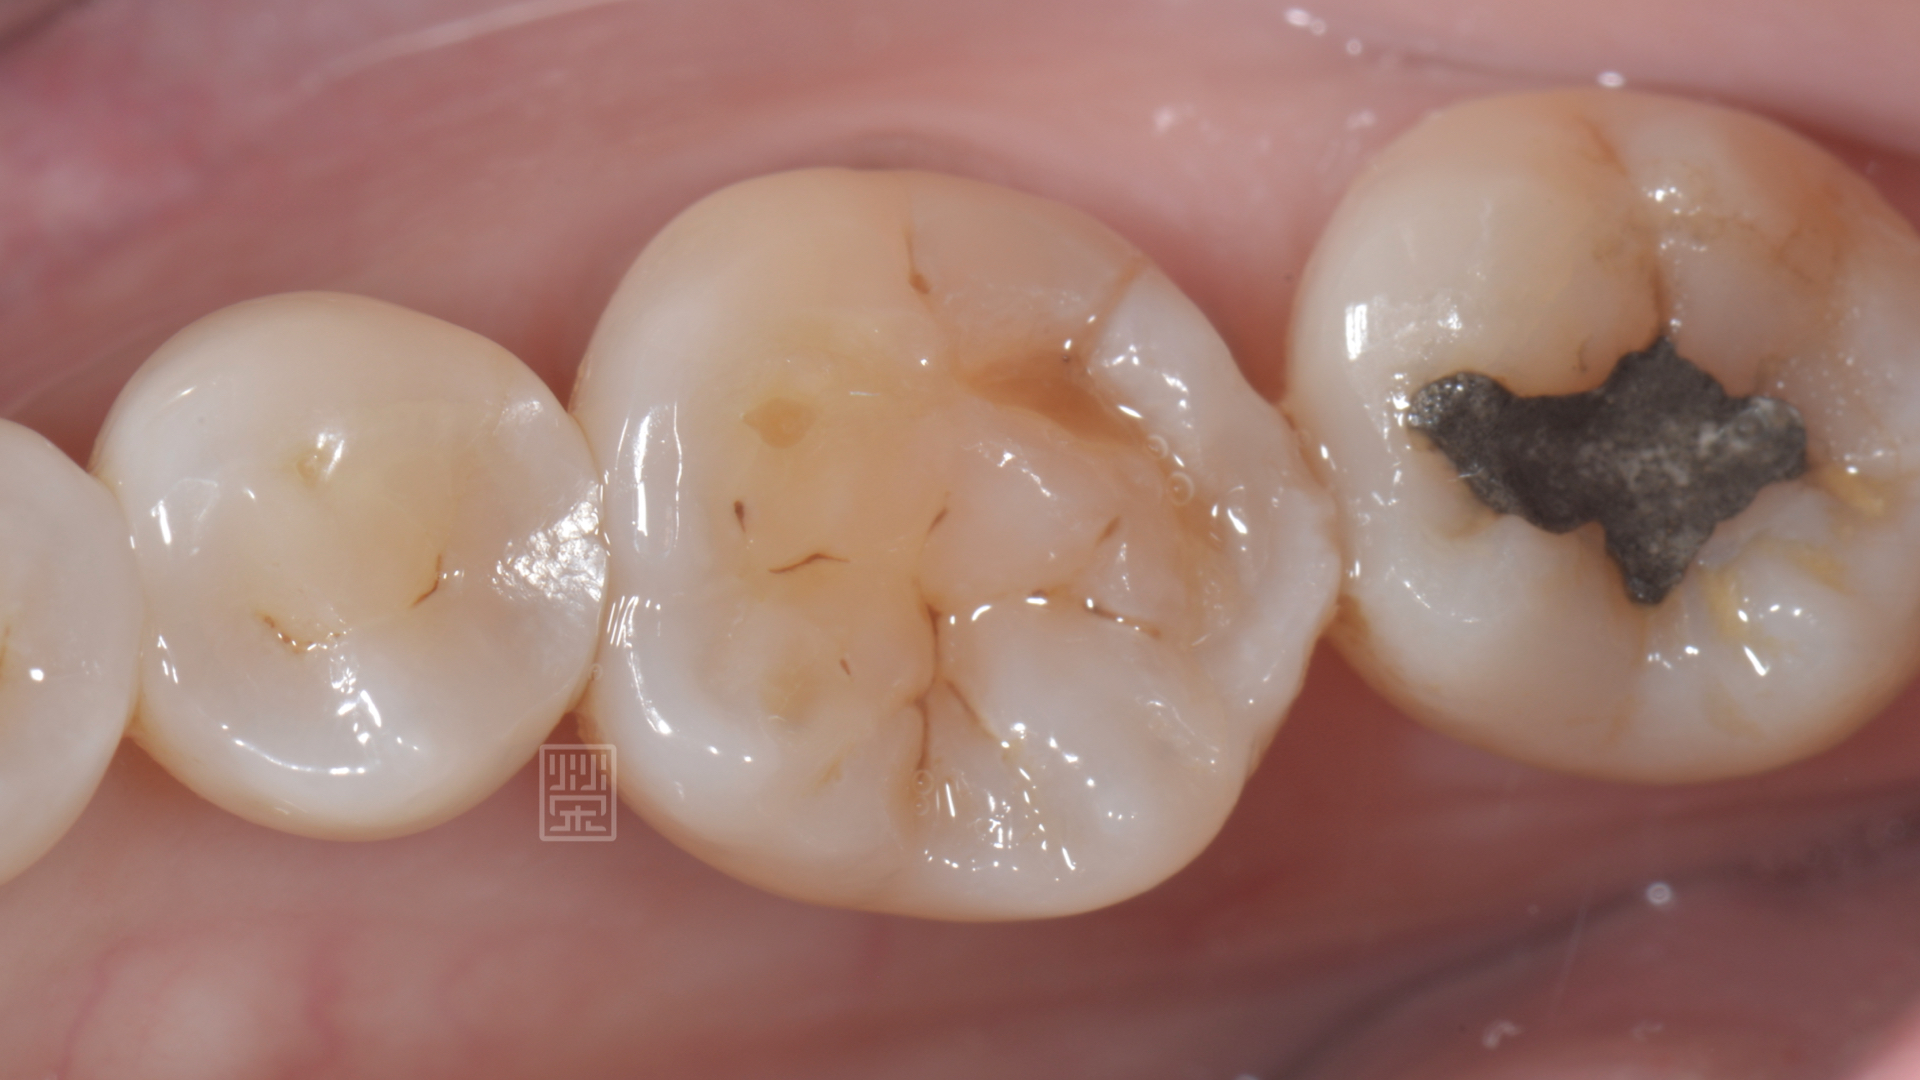

楊女士因為上顎第二大臼齒缺牙,所以咬合重心都是在第一大臼齒咬合對,前陣子突然發覺咬東西有點痛痛的,以為是牙齦發炎,認真刷牙後,狀況並未改善,來榮醫師診間就診,發現除了咬合面明顯磨耗,牙本質都裸露之外,頰側面有明顯的縱向裂痕,還好的是牙齒神經並未造成不可逆傷害,建議製作全瓷嵌體,將牙齒戴上保護罩,減少治療過程牙齒的傷害。

咬合面耗損